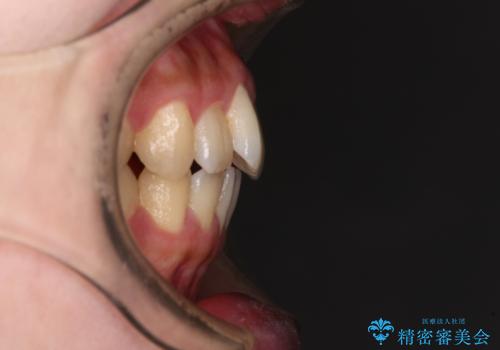

- 捻れた前歯が飛び出しており、口が閉じにくいとのことで来院された患者様です。

出っ歯というわけではないものの、前歯の捻転により口唇が押し出されている状態でした。

親知らずを抜去し、歯列全体を後方に移動させつつ、IPR(歯と歯の間を削る)でスペースを獲得し、インビザラインを用いて叢生を解消しながら前歯の突出を改善することとしました。